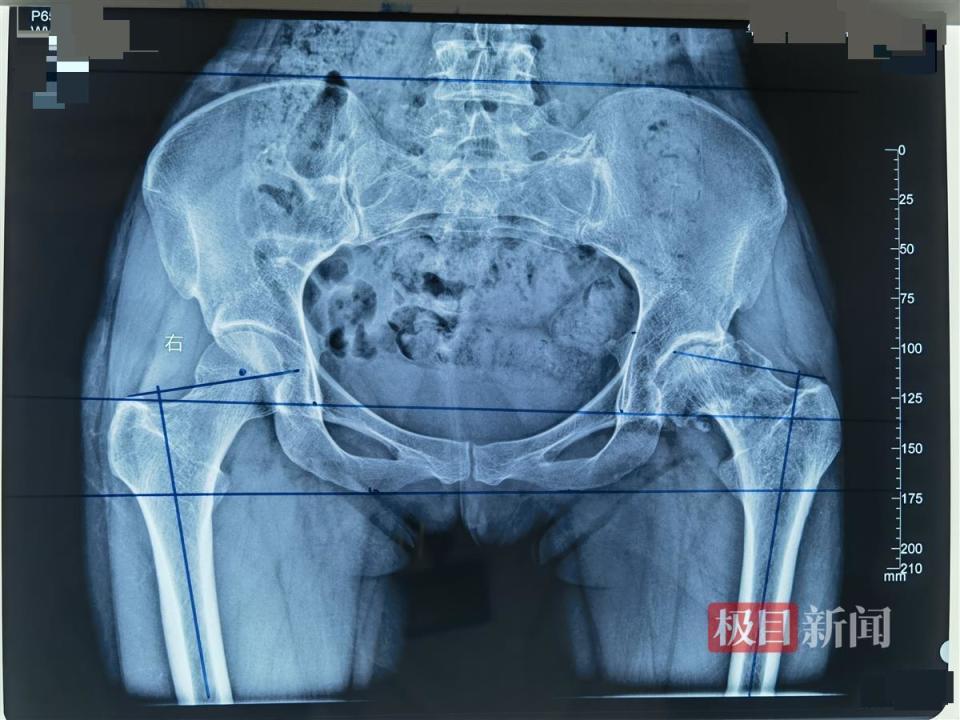

女子股骨头坏死多年,她在协和车谷院区换了髋关节,两个月后重返健身房

股骨粗隆间骨折的全髋关节置换